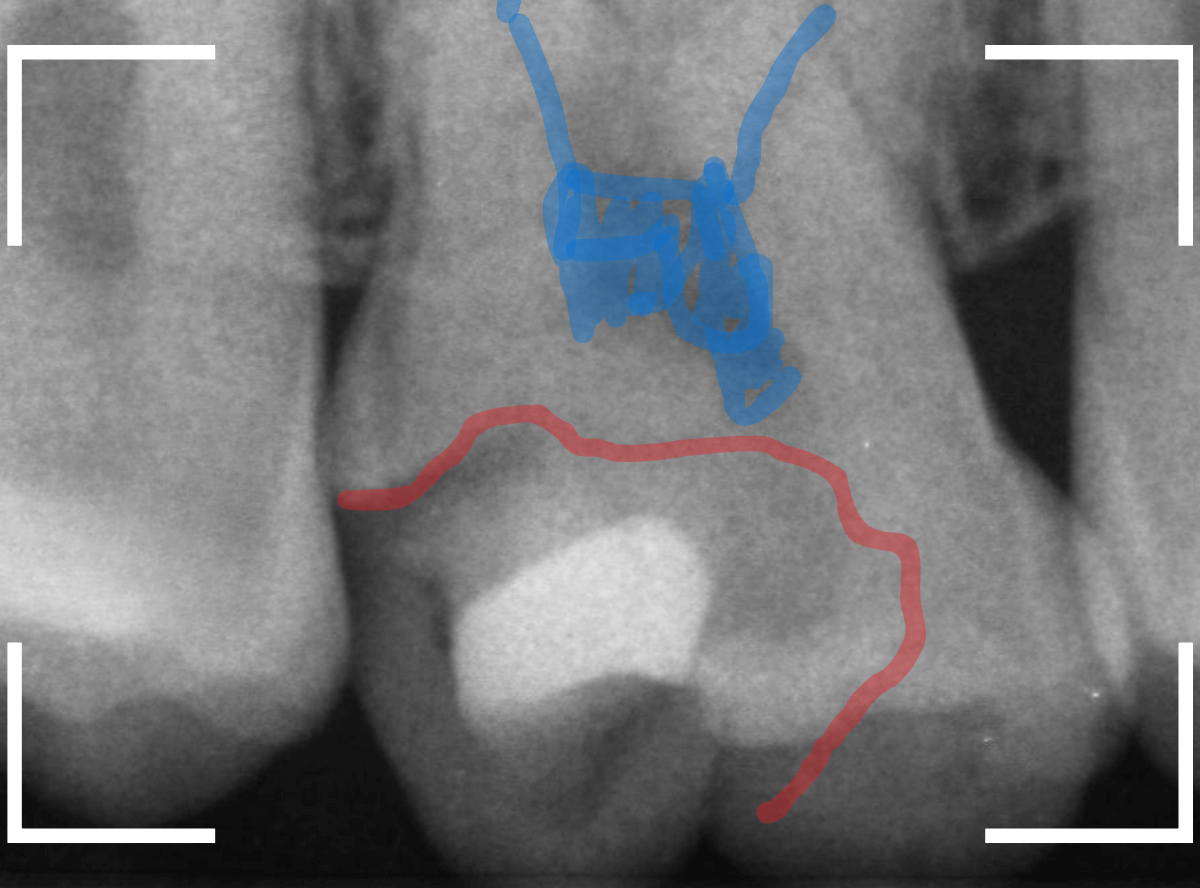

虫歯の治療のブログでも紹介した症例ですが、レントゲン写真で、破折したレジンの中で神経の近くまで虫歯になっているのがわかります。

神経に近い虫歯ですので、いつも以上に慎重に虫歯をある程度除去したところで、虫歯の状況を検知液で確認します。

薄く赤く染まっているところが虫歯です。

逆に、他の色がついているところは、虫歯ではないので、削らなくてもよいという事ですね。

全く染色されなくなりました。

これで全ての虫歯を除去したことになります。